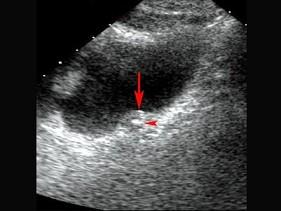

问题 男,25岁,左腰痛2小时伴镜下血尿,超声显示左肾盂左输尿管轻度扩张,膀胱超声图如下,可提示诊断是?(?)

选项 A.左输尿管囊肿 B.左输尿管结石 C.左输尿管肿瘤 D.左输尿管狭窄 E.以上都不是

答案 B